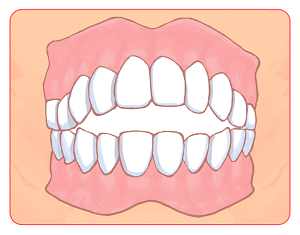

「いびき」と「口輪筋」の関係

「いびき」と「口輪筋」の関係